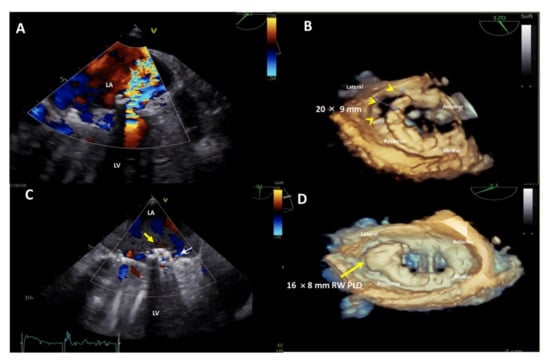

A further advantage of the rectangular-shaped PLD is the option to close large defects (Figure 6) or even multiple leaks located in close proximity with one single device.

Figure 6.

Upper panel: baseline 2D Transesophageal Echocardiogram (TEE) color Doppler showing a severe paravalvular leak (PVL) regurgitant jet into the left atrium (A) and 3D TEE showing a huge, 20 × 9 mm in diameter, crescent-shaped, antero-laterally located (7–10 o’clock) mitral PVL after bileaflet mechanical valve replacement (B). Lower panel: post-procedure 2D TEE color Doppler showing the correct position of the device (C, yellow arrow) with a trace-mild residual regurgitant jet (C, small white arrow) and 3D TEE confirming the stable position of the 16 × 8 mm-rectangular waist PLD (yellow arrow), without impingement on the mechanical prosthetic mitral valve (D). LA, left atrium; LV, left ventricle; PLD, Occlutech Paravalvular Leak Device; RW, rectangular waist.

Indeed, in 87.5% of the patients with two Ao PVLs, one single device was used for leak closure. Similarly, in 33.3% of the patients with two Mi PVLs and in 20.0% of patients with three Mi PVLs, fewer devices than the number of leaks were used. This is a clear advantage compared to using multiple smaller devices in terms of stability, procedure-time and costs and confirms the findings previously reported by Goktekin et al. [23], who reported that the rectangular shape was associated with a higher success rate. The primary performance endpoint of this study is the proper closure of the PVL, defined as a reduction in paravalvular regurgitation by ≥1 grade at 180 days post implantation and/or reduction in the number of hemolysis related transfusions 6 months after the procedure.